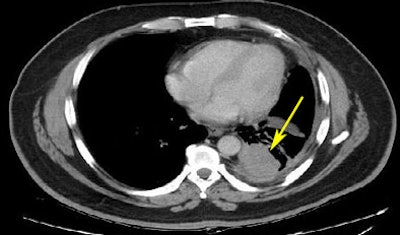

![]() |

| A lung nodule unmarked (top) and marked (bottom) from the LIDC database. All images courtesy of the National Cancer Institute. |